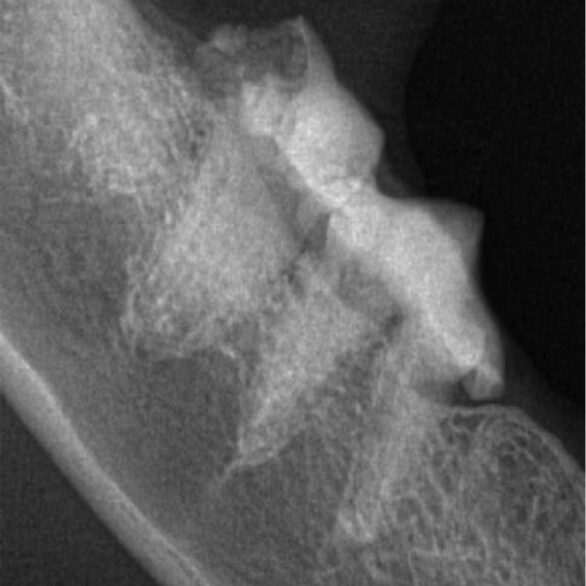

Because they start below the gum line the most sensitive way to diagnose a FORL is with radiographs, using a specialised dental X-ray system to allow us to locate and diagnose the lesions before going to surgery, minimising the risk of damage to the delicate tooth roots. FORLs may be visible above the gum line during routine examination at the vets, during dental surgery, or because an apparently healthy tooth has snapped off.

The images below are radiograph images and demonstrate how this technique is used to identify the condition. The image on the left shows healthy teeth, whereas the image on the right shows lesions and the progression of resorption.